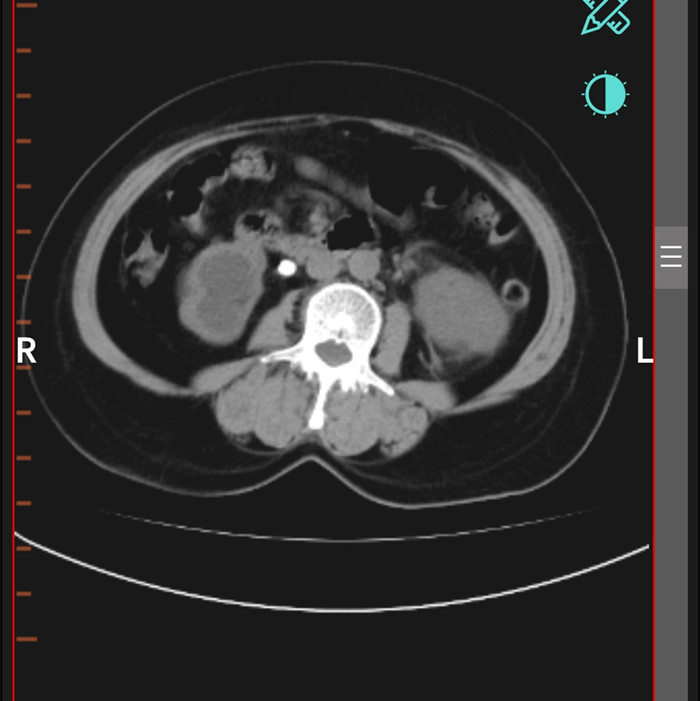

柴女士,62歲,北川縣擂鼓鎮(zhèn)人,因腰右側(cè)疼痛難忍,她來到北川羌族自治縣人民醫(yī)院就診,經(jīng)檢查提示,柴女士右輸尿管上段結(jié)石嵌頓引起重度腎積水。

“要及時解除梗阻,可以行腹腔鏡輸尿管切開取石術(shù)取代開放手術(shù)?!痹谥靹τ碌膸ьI(lǐng)下,這支剛剛成立的“泌尿外科團隊”,僅用了一個半小時就完成了手術(shù)。“腹腔鏡輸尿管切開取石術(shù)創(chuàng)傷小,患者腰腹部只有3個戳孔,術(shù)后恢復(fù)快?!敝靹τ抡f。